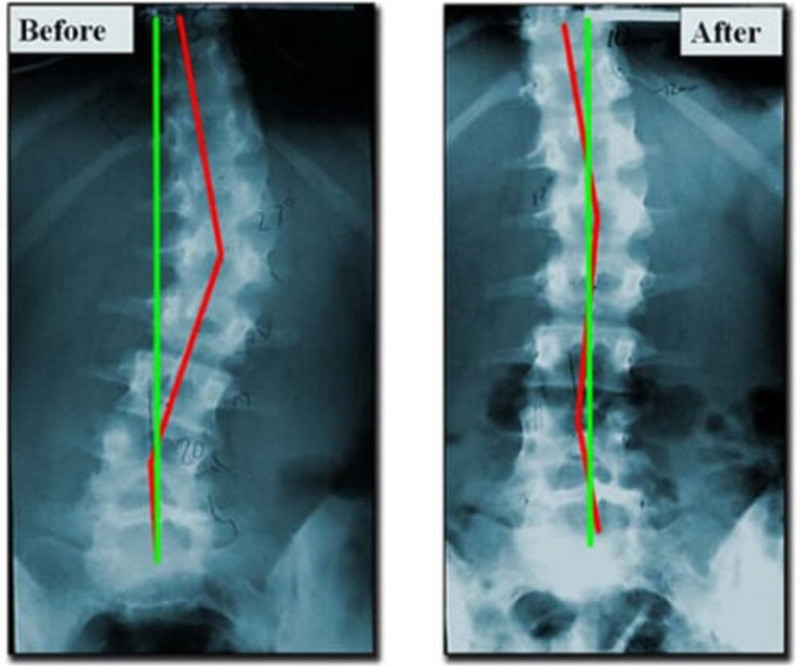

Rayos X de la columna vertebral

Tratamiento correctivo de columna vertebral